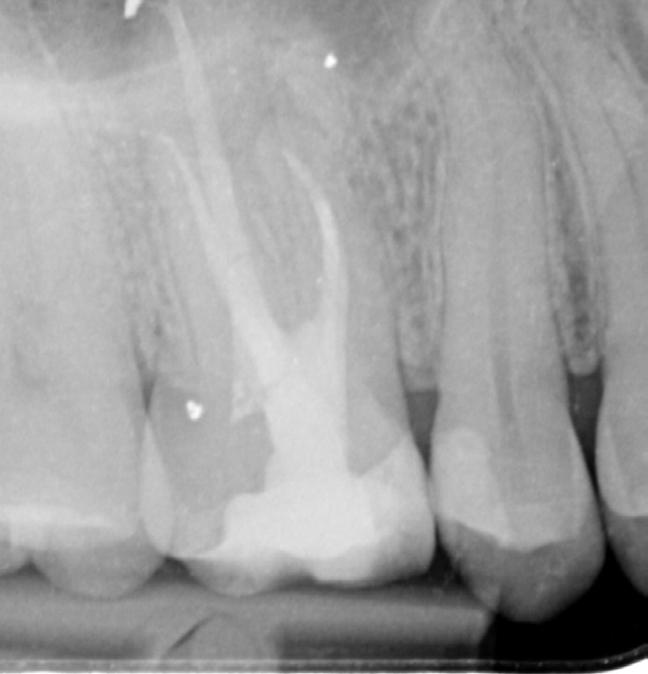

• Diagnose: aandachtspunten bij het mondonderzoek, inschatten van het cariësrisico en frequentie van bitewings

• Interpretatie van bitewings: wanneer behandelen en wanneer niet; bijzondere gevallen

We bespreken heel veel röntgenfoto’s en casussen. Ook voor jouw eigen casus(sen) maken we ruimte. Ook gaan we de praktijk in: je doet een PMO bij een van je medecursisten en past toe wat je eerder deze lesdag geleerd hebt.